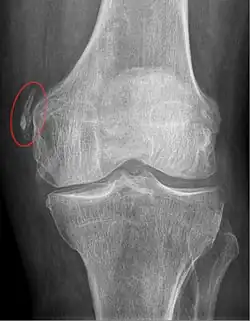

Pellegrini–Stieda syndrome (also called Stieda disease and Köhler–Pellegrini–Stieda disease) is the ossification of the superior part of the medial collateral ligament of the knee. It is a common incidental finding on knee radiographs. It is named for the Italian surgeon A. Pellegrini (b. 1877) and the German surgeon A. Stieda (1869–1945).[1] While the eponym refers to Pellegrini and Stieda, the condition was first discovered by Köhler in 1903, before any namesakes. Pellegrini-Stieda combines the aforementioned radiographic findings and concomitant medial knee joint pain or restricted range of motion.[2]

Diagnosis is typically made on radiographs demonstrating the Pellegrini-Stieda syndrome sign accompanied by pain or restriction of range-of-motion of the knee joint.[2] Pellegrini-Stieda syndrome sign is typically described by a longitudinally linear opacity, which is a process that is describes characteristic of calcification in the soft tissue located medial to the medial femoral condyle.[2] This calcification seen on imaging represents the ossification of the medial collateral ligament, which typically does not develop until approximately three weeks after the initial injury.[2]It is important to note to distinguish this radiographic finding from that of a medial femoral condyle avulsion fracture, which is an injury in which a pulling force of a tendon or ligament fractures away a piece of the bone from its attachment site.[2]

Alternative classification syndrome for Pellegrini-Stieda lesions of Type 1 through Type 4 based on their location:[2]

- Type 1- is referred to as a beak-like appearance and describes the ossification arising from the femur and extending inferiorly in the medial collateral ligament.

- Type 2-is defines a tear-drop pattern, localized within the medial collateral ligament without any attachment to the femur.

- Type 3-presents as an elongated ossification superior to the femur lying in the distal adductor magnus tendon.

- Type 4-is also characterized as a beak-like appearance arising from the femur. However, there are some cases where this ossification extends into both the medial collateral ligament and adductor magnus tendon. In then, the original attribution of the syndrome to the medial collateral ligament may now be outdated as many publications have suggested concomitant and even sometimes preferential involvement of the adductor magnus tendon, medial head of the gastrocnemius, or medial patellofemoral ligament.[2]